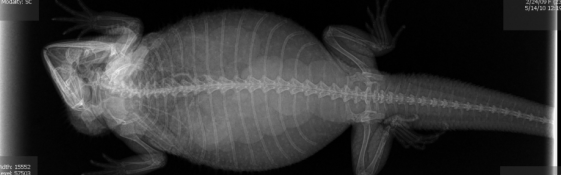

▼怀孕的狗狗